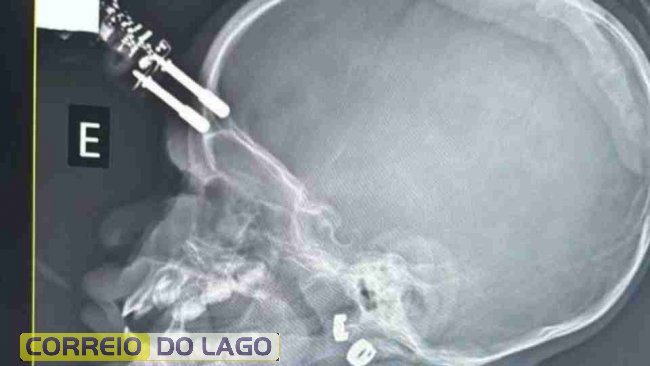

Bebê fica com carregador cravado na testa após cair de cama

Exames de imagem apontaram que o objeto atravessou o crânio

Exames de imagem apontaram que o objeto atravessou o crânio, o que levou a equipe médica a encaminhar a menina imediatamente para o bloco cirúrgico. O procedimento foi realizado para a retirada segura do corpo estranho e para evitar complicações neurológicas. Após a cirurgia, a criança permaneceu 36 horas no Centro de Terapia Intensiva (CTI) e, na sequência, recebeu alta médica, sem sinais aparentes de sequelas.